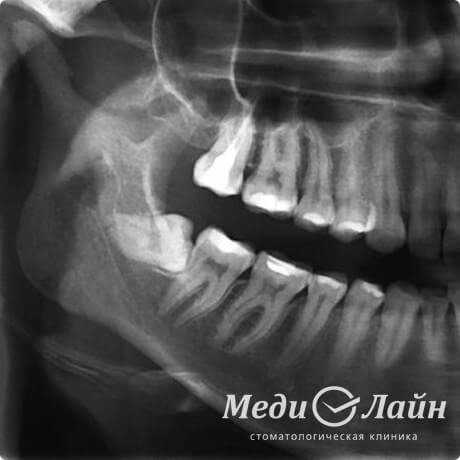

Что такое «лежачие восьмёрки»?

«Лежачие восьмёрки» — это зубы, которые растут в горизонтальном положении внутри челюсти. Они доставляют болезненные и неприятные ощущения, потому что давят на соседние зубы, а это ведёт к смещению всего зубного ряда и постепенному разрушению рядом стоящих седьмых зубов.

Классическое удаление «лежачей восьмерки» довольно затруднительно даже для опытного врача, но ультразвуковой пьезоскальпель легко справляется и с такой сложной задачей.

Лежачие восьмерки